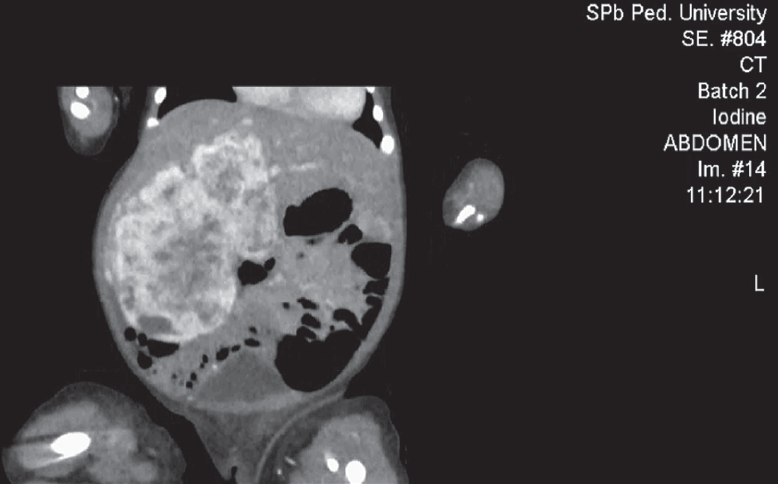

Hemangiomas are the most frequent tumors of childhood age. In the first year of life their prevalence is 10–12%. Among premature children, the prevalence of hemangiomas correlates with the degree of prematurity. Liver hemangiomas are a wide range of benign vascular formations that can acquire both malignant course and capable of spontaneous regression. Small-sized hemangiomas generally do not require specific treatment and proceed asymptomally. Large-sized formations can cause life-threatening conditions such as severe thrombocytopenia with coagulopathy (Kazabah–Merrit syndrome), anaemia, tumor hemorrhage, spontaneous and traumatic tumor breaks, heart failure associated with intra-tumor bypass of blood flow, abdominal compression syndrome, severe hypothyroidism. Diagnosis of this pathology is carried out on the basis of a set of data of medical imaging, laboratory diagnostics and clinical picture. This review presents key points of general classification, the most characteristic diagnostic signs, as well as basic algorithms of treatment of liver hemangiomas in newborns and children of the first year of life. There are also described 2 clinical cases of newborns with giant liver hemangiomas, which were examined and treated in the pathology department of newborns and infants of Perinatal Center of St. Petersburg State Pediatric Medical University with a description of the peculiarities of the course of each of them.